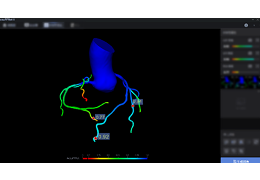

分析智能。

这些功能利用数字控制面板分析运营、业务和临床绩效。

使管理员能够跟踪关键参数,包括平均曝光率、拒绝的影像和探测器统计信息。

帮助确定需要改进的方面,支持为员工和部门制定适当的改进计划。